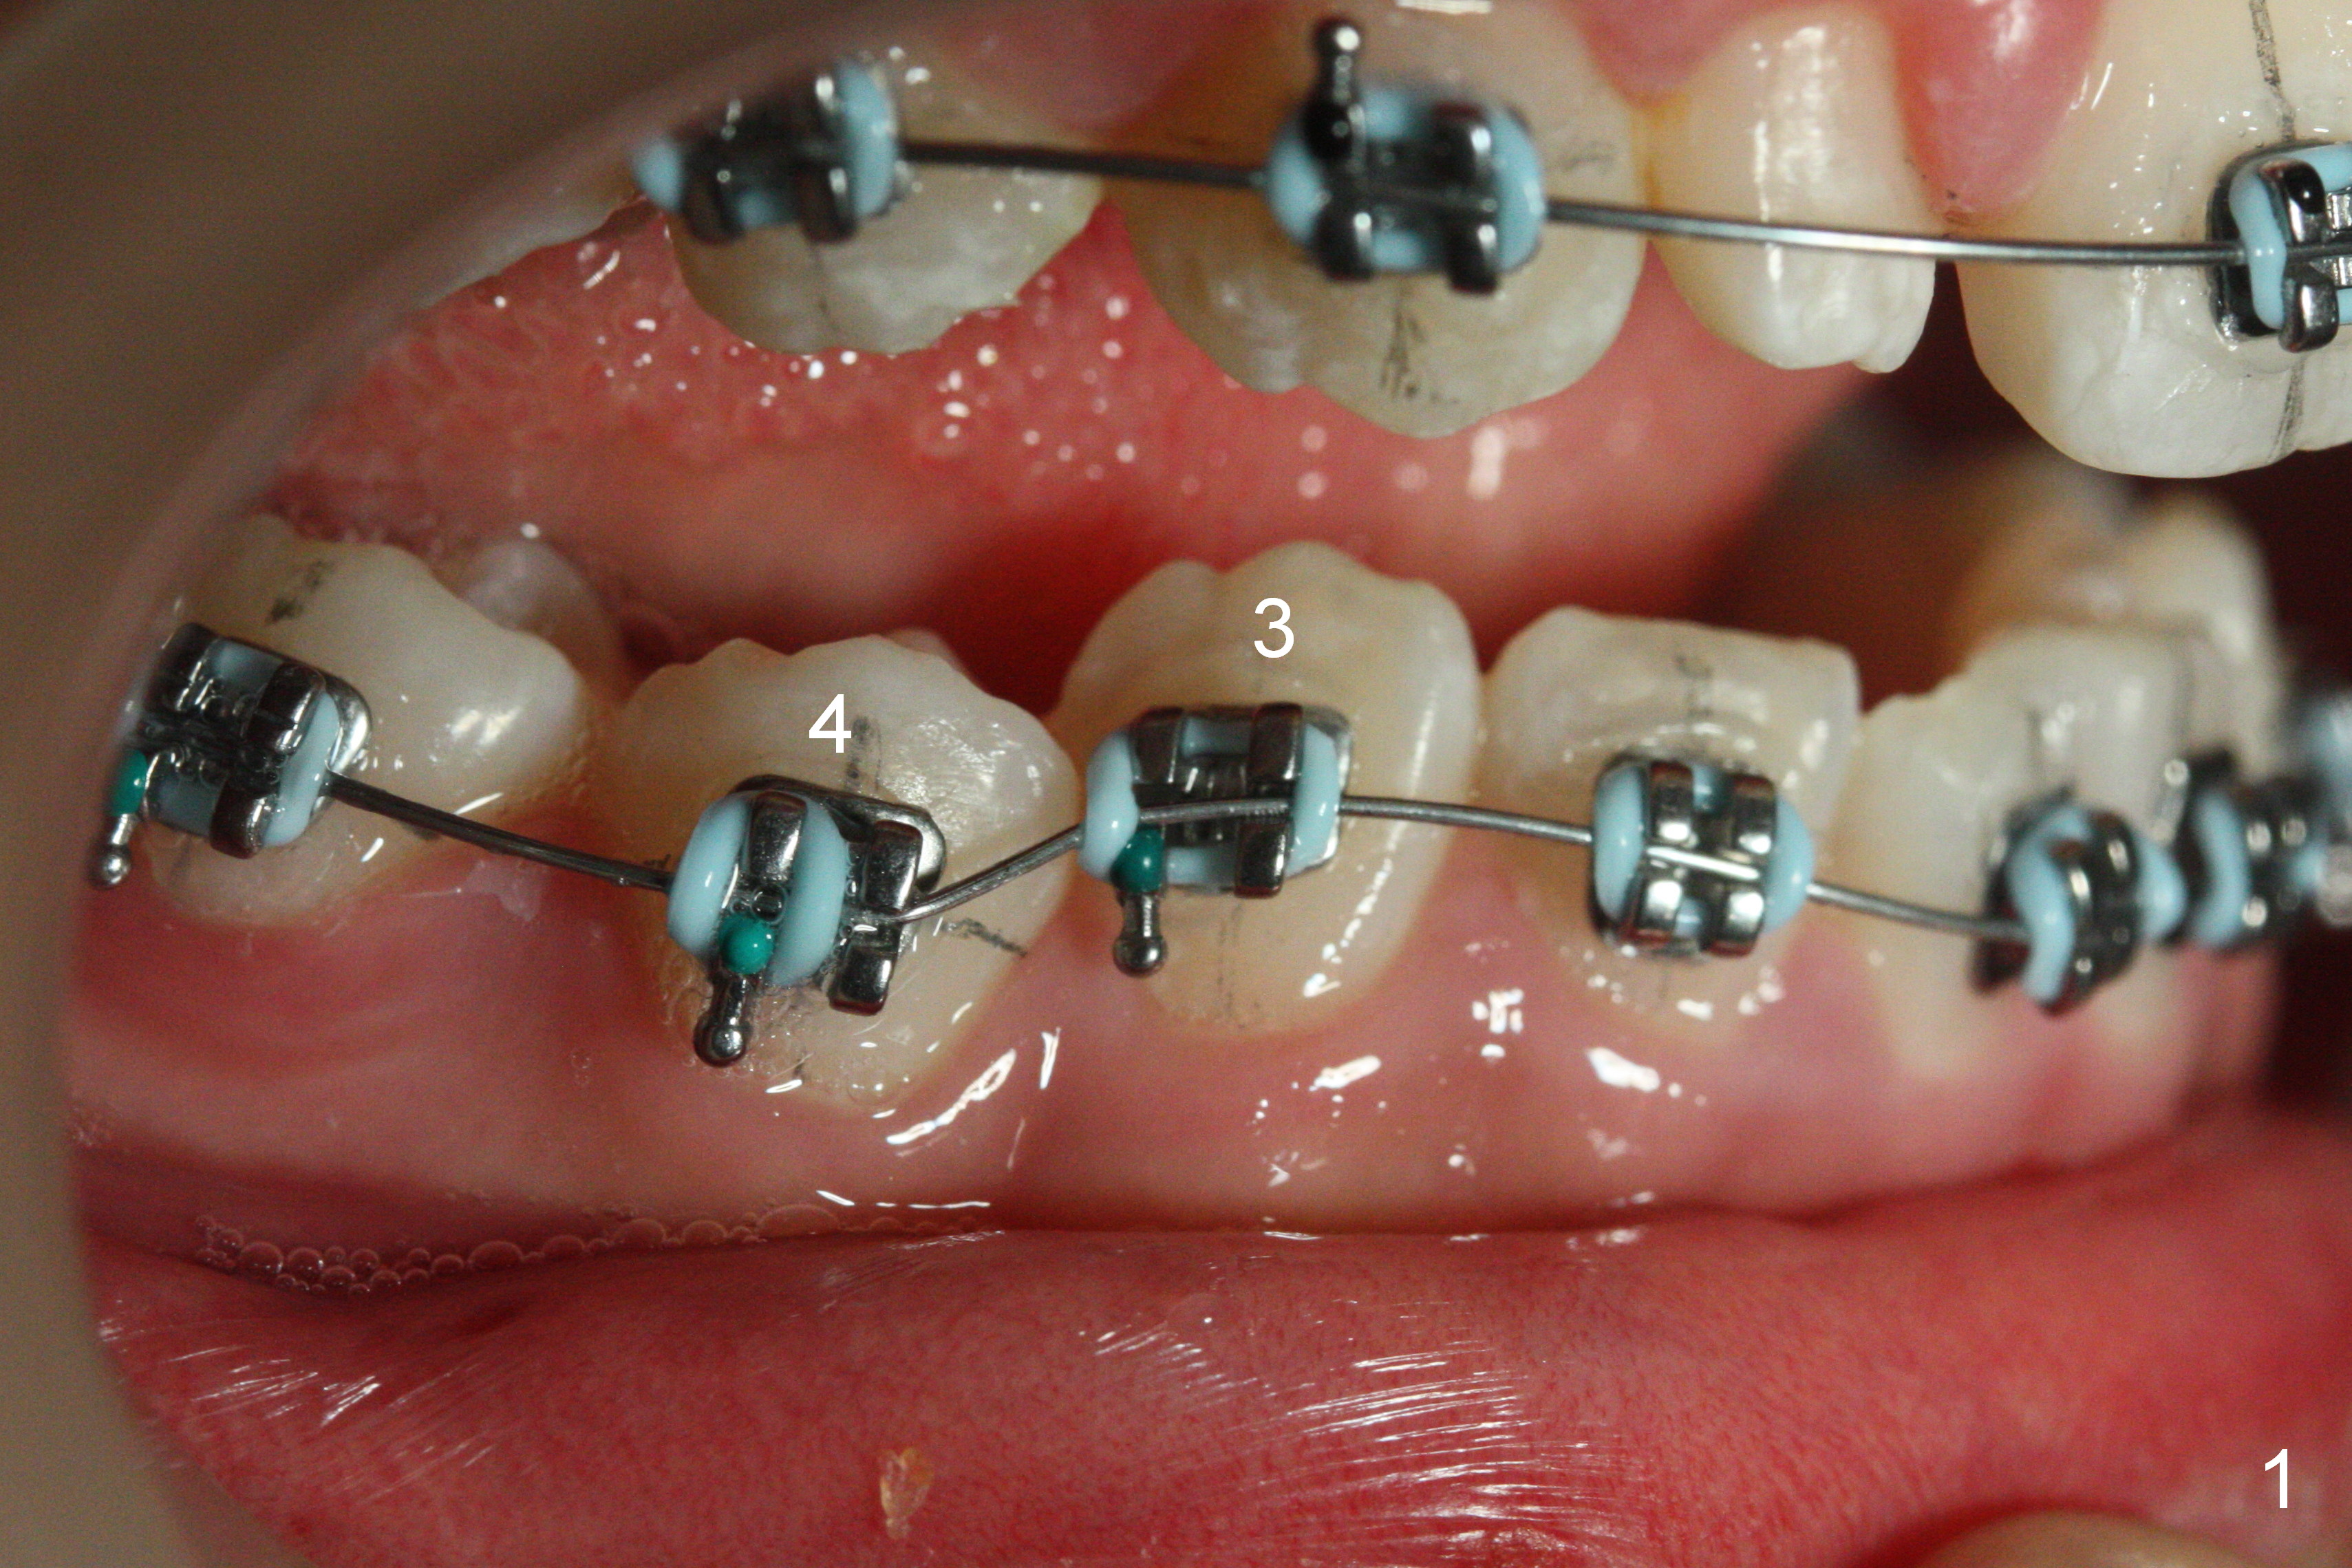

As planned, the peg laterals do not have brackets placed (Fig.2), since their position and shape will be ultimately decided by veneers. Alignment of the lower arch is more severe than that of the upper one, characterized by severe crowding at LR 3 and 4 (Fig.1) and rotation of LL 5 (Fig.3). Oral hygiene does not improve during orthodontic treatment. Impression will be taken prior to debanding. Space is obtained for LL2; brackets are placed at LL2 and 5; 14 niti wire is placed 9 months post banding (Fig.4-6). Orthodontic treatment is terminated prematurely partially due to poor oral hygiene.